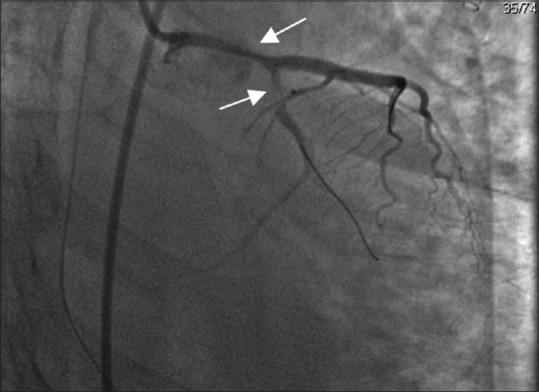

Spontaneous coronary artery dissection is becoming an important cause of acute coronary syndrome, particularly among young women. Its association with female gender, pregnancy, and postpartum period and emotional stress differentiate it from atherosclerotic heart disease. In recent years, there has been more awareness and improved diagnostic and management capabilities, which in turn has increased the diagnostic yield, although knowledge gaps remain. In the present case, a 36-year-old female, who was at 1-month postpartum period, presented with ventricular fibrillation and cardiac arrest. The clinical course was associated with pulmonary hemorrhage. The patient had no current atherosclerotic risk factors, only a family history of sudden cardiac arrest in her mother and sister. She underwent a coronary angiogram, which revealed spontaneous coronary artery dissection (SCAD) in both the left anterior descending and left circumflex artery. Percutaneous coronary intervention was performed but the clinical course was associated with pulmonary hemorrhage. Bronchopulmonary lavage was performed as a diagnostic and therapeutic intervention, and she was discharged in good health. SCAD is an important differential diagnosis in young females presenting with acute coronary syndrome or cardiac arrest. Early recognition and diagnosis are important to decrease the high mortality rate of this disease.

自发性冠状动脉夹层正成为急性冠状动脉综合征的一个重要病因,尤其是在年轻女性中。它与女性性别、妊娠、产后时期以及情绪应激的关联使其有别于动脉粥样硬化性心脏病。近年来,人们对此病的认识有所提高,诊断和管理能力也有所改善,这反过来提高了诊断率,尽管仍存在知识空白。在本病例中,一名36岁处于产后1个月的女性出现心室颤动和心脏骤停。临床过程伴有肺出血。该患者目前没有动脉粥样硬化危险因素,仅有其母亲和姐姐有心脏骤停家族史。她接受了冠状动脉造影,结果显示左前降支和左旋支均有自发性冠状动脉夹层(SCAD)。进行了经皮冠状动脉介入治疗,但临床过程伴有肺出血。进行了支气管肺灌洗作为诊断和治疗干预,她最终健康出院。SCAD是年轻女性出现急性冠状动脉综合征或心脏骤停时的一个重要鉴别诊断。早期识别和诊断对于降低该病的高死亡率很重要。